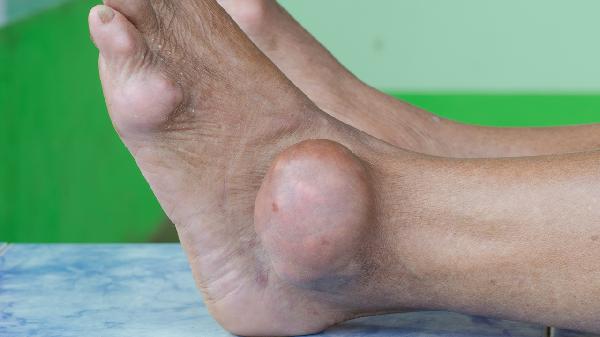

大腳骨通常指拇外翻,其最佳治療方法需根據(jù)畸形程度選擇,輕度畸形可通過保守方式改善,中重度畸形則需手術(shù)矯正。

對(duì)于輕度拇外翻,畸形角度較小且疼痛輕微,通常采用非手術(shù)干預(yù)。更換寬松舒適的鞋子有助于減輕對(duì)拇囊的擠壓,緩解局部疼痛。定制矯形器或分趾墊可改善腳趾排列,延緩畸形進(jìn)展。疼痛發(fā)作時(shí)進(jìn)行局部冰敷能減輕炎癥反應(yīng),每日數(shù)次,每次不超過15分鐘。物理治療如腳趾抓毛巾訓(xùn)練可增強(qiáng)足底肌群力量,改善生物力學(xué)平衡。這些方法適用于早期患者,需要長期堅(jiān)持才能維持效果。

中度拇外翻伴隨明顯疼痛和行走困難,需考慮手術(shù)治療。軟組織重建術(shù)適用于關(guān)節(jié)松弛但畸形角度尚可的患者,通過調(diào)整肌腱張力恢復(fù)平衡。Chevron截骨術(shù)針對(duì)中度畸形,在跖骨頭處進(jìn)行V形截骨并移位固定。Scarf截骨術(shù)通過Z形截骨實(shí)現(xiàn)三維矯正,適用于更復(fù)雜的畸形。關(guān)節(jié)融合術(shù)用于嚴(yán)重關(guān)節(jié)炎患者,能有效緩解疼痛但會(huì)喪失關(guān)節(jié)活動(dòng)度。微創(chuàng)手術(shù)具有創(chuàng)傷小、恢復(fù)快的優(yōu)勢(shì),但需嚴(yán)格掌握適應(yīng)證。